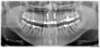

Patient de 40 ans venu pour reconstituer ses incisives supérieures abimées par un choc.

La planification est réalisée par ordinateur, les dents sont enlevées, les implants posés dans la même séance, sans chirurgie traumatique.

La prothèse provisoire esthétique est posée le soir même. Elle est fixe.

Elle sera remplacée par une prothèse définitive céramique entre 3 et 6 mois